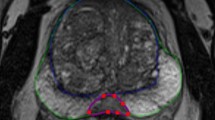

Manual delineation

All 74 individual lesions were manually delineated on T2WI for both scans based on PI-RADS reports by a radiology resident (E.S.) with over 5 years of experience in examining PCa lesions at St. Olavs Hospital, Trondheim University Hospital, Trondheim, Norway using ITK-SNAP [25] (v3.6).